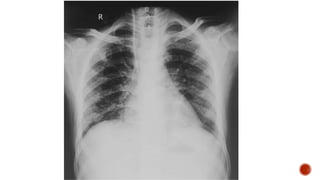

Frontal chest radiograph shows few ill defined patchy opacities in both the lung

fields, few of them showing cavitatory changes. TCC seen in situ.

Compared to the previous radiograph there is reduction in the number of opacities

with cavitatory changes.

 Malignancy:

 Squamous cell carcinoma of the lung

 Metastasis :

 squamous cell ca

 adenoca from GIT/breast

 sarcoma

 cervical carcinoma

 urothelial carcinoma of the bladder

 Infection :

 Septic embolism

 Pulmonary tuberculosis

 Abscess

 Post pneumonic pneumatocele

 Necrotizing pneumonia

 Autoimmune :

 Wegeners granulomatosis

 Rheumatoid nodules